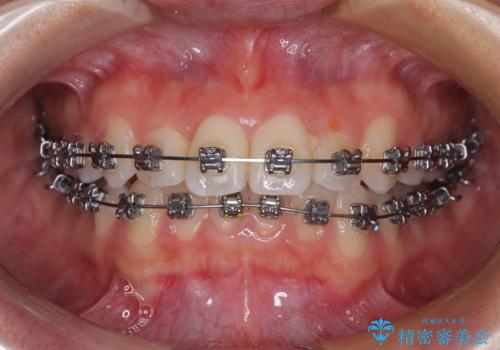

- 矯正装置

- メタルブラケット

装置の外見を気にしていましたが、短期間で治療を終えることができるだろうと伝えると、安価であるメタルブラケットを選択されました。

想定通り、1年強で綺麗に仕上げることができました。